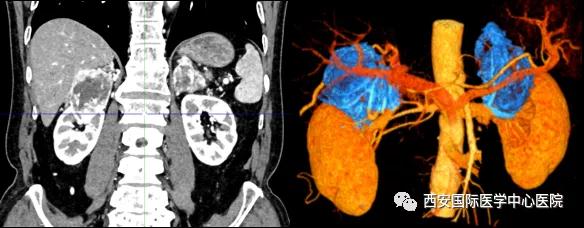

今年七十五歲的患者,來自陜西省商洛市,四月前因腰背部疼痛就診于當(dāng)?shù)蒯t(yī)院,行CT檢查發(fā)現(xiàn)“右腎、雙側(cè)腎上腺占位,前縱膈淋巴結(jié)腫大,雙肺多發(fā)結(jié)節(jié)、胸椎骨質(zhì)破壞,考慮轉(zhuǎn)移瘤”。為進(jìn)一步診斷治療,患者的兒子帶他來到西安某三甲醫(yī)院,查泌尿系CT提示“右腎占位性病變,多考慮腎癌,雙側(cè)腎上腺多發(fā)轉(zhuǎn)移灶,腹膜后多發(fā)腫大淋巴結(jié)”;行穿刺活檢提示“腎透明細(xì)胞癌”;并給予患者口服靶向藥物的治療方案。

自四月份至今,患者一直口服靶向藥物治療(阿昔替尼5mg 2次/日),期間無不良反應(yīng),目前腰背部疼痛癥狀也有所緩解,復(fù)查影像學(xué)資料提示瘤體較前縮小,腫瘤完整切除的可能性明顯提高;而且患者的兒子也是一名外科醫(yī)生,所以他更想為父親完成后續(xù)的手術(shù)治療。

手術(shù)由楊增悅教授主持,舒濤主治醫(yī)師、王東主治醫(yī)師主刀,黃怡醫(yī)師、王平醫(yī)師協(xié)助完成。由于第四代達(dá)芬奇機(jī)器人更加靈活和精準(zhǔn)的特性,手術(shù)全程順利,尤其是完全精準(zhǔn)的“解鎖”了右腎動脈和右腎靜脈的數(shù)十根交互纏繞的分支血管。術(shù)后患者麻醉恢復(fù)后生命體征平穩(wěn),順利返回泌尿外科普通病區(qū)進(jìn)一步康復(fù)。